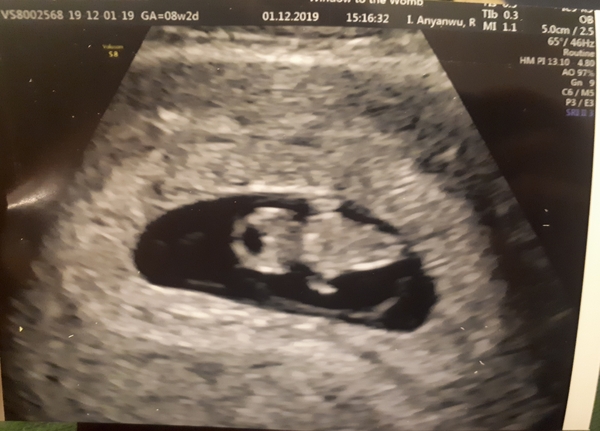

I had my early scan today! So relieved...

Little one is measuring 7+6, so spot on what I thought! All is well, strong heartbeat etc.. EDD 13th July :)

@Julilie72 Lovely scan! Much clearer than my 8 week scan. Can clearly see the head and arms on yours! Mine was still a blob lol. Was yours external?